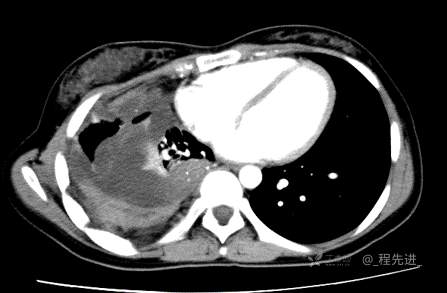

患者性别:女

患者年龄:26岁

简要病史:反复胸闷、气喘、咳嗽半年